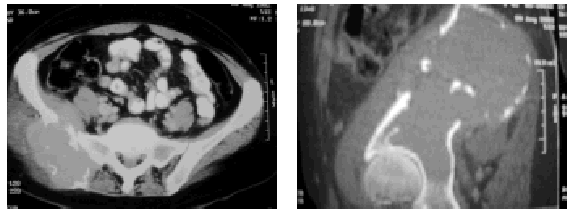

En el estudio radiológico encontramos: imagen patológica en pala ilíaca derecha, que se estudia con tomografía axial computarizada (TAC) existiendo una lesión expansiva de 17 x 7 cm que rompe la cortical e infiltra la musculatura, existiendo gran osteólisis del ilíaco (fig. 1), siendo radiológicamente compatible con un osteosarcoma.

Fig. 1. Tomografía axial computarizada en la que se observa lesión osteolítica de pelvis con afectación de partes blandas.